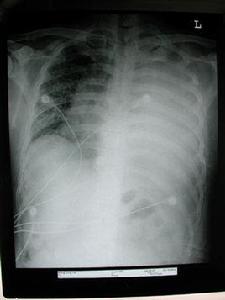

對惡性胸水做胸部X線攝片是最基礎的檢查,肋膈角變鈍提示有少量積液;大量胸水常伴有肺不張和縱隔向腱側移位,如縱隔因腫瘤固定,則縱隔移位不明顯。超聲檢查對確定胸水的含量、胸水是否包裹、知道穿刺進針方向和進針深度等均有重要意義。